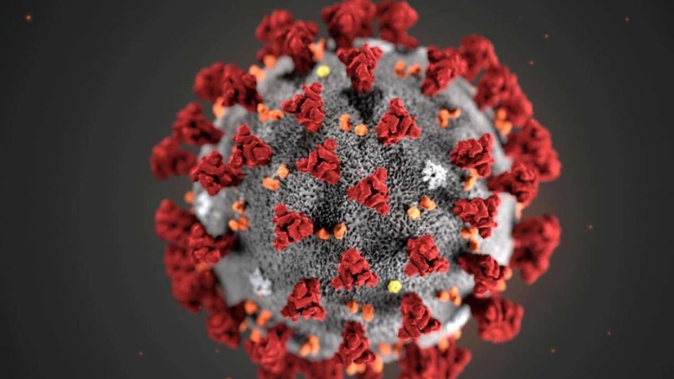

The latest variant of Covid-19 emerging in other parts of the world including the UK is estimated to be 10 times more transmissible than its predecessors.

Omicron XE first appeared in the UK in mid-January and is a hybrid of Omicron BA.1 and the more transmissible BA.2 – the dominant strain currently in New Zealand.

University of Otago evolutionary virologist Dr Jemma Geoghegan said recombinants – new variants caused by mixing different strains – were common and occurred when viruses infected the same person at the same time allowing the viruses to interact during that replication process. Sometimes their genetic material can get mixed up and that resulted in the combinations being formed.

The Covid-19 virus had been recombining throughout the whole pandemic, but the higher number of cases probably made it easier to spot.

So far there were about 17 recombinants that had been given names and they were either a combination of Delta and Omicron or Omicron subvariants.

Geoghegan said while UK scientists had noted XE could be between five and 10 per cent more transmissible, it was still early science and needed to be reconfirmed with more data.

It was also very likely that XE would possess the same characteristics as the variants they were made from – BA.1 and BA.2 – so carry the same disease severity and have the same response to vaccines.

The World Health Organisation said XE still belonged to the Omicron variant until significant differences in transmission and disease characteristics, including severity, were found.

As of March 25, there were more than 600 confirmed cases in the UK. The variant has also recently been detected in Thailand, according to the Bangkok Post.

As well as XE, two other new variants XD and XF – both a combination of Delta and Omicron BA.1 – have also popped up around the world.

In the UK, only 38 cases of XF have been identified but not since mid-February, while a similar number of XD have been reported in France. There was no evidence of wide transmission of either of these.